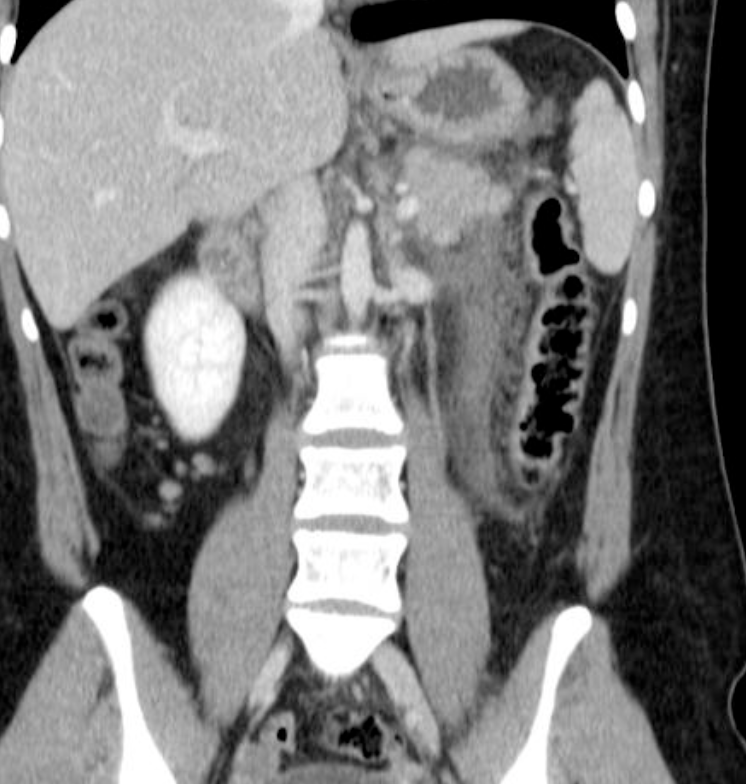

Findings: A well-defined rounded exophytic cystic lesion measuring 6.3 x 7 x 7 cm is seen originating from the tail of the pancreas. It has an average density of 8 HU and shows mild peripheral enhancement on post contrast study. A few thin septations and a tiny mural calcification are seen in it. No solid component is seen in it. Morphology of the remaining pancreas is unremarkable.

Impression: Well-defined rounded exophytic cystic lesion originating from the tail of the pancreas, which is likely, a mucinous cystadenoma of the pancreas (mucinous cystic neoplasm of the pancreas) with possible differential diagnosis of pancreatic pseudocyst (if there is a past history of pancreatitis). Another possible differential can be a hydatid cyst which is however, very unlikely.